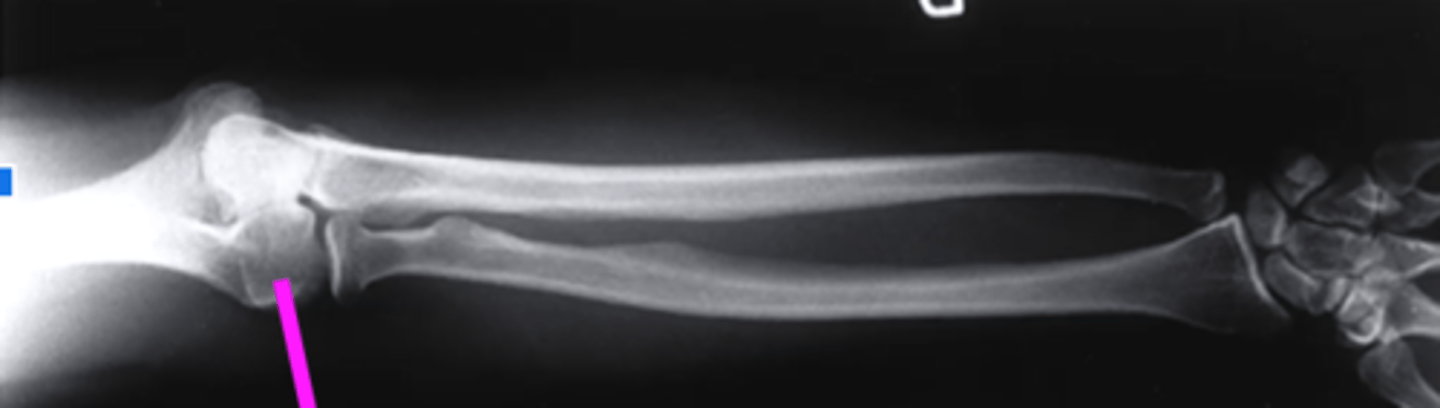

AP forearm

what view is this?

olecranon process

what does this pink line point to?

trochlea

capitulum

humeroradial joint

proximal radioulnar joint

radial tuberosity

radial styloid

distal radioulnar joint

scaphoid

lunate